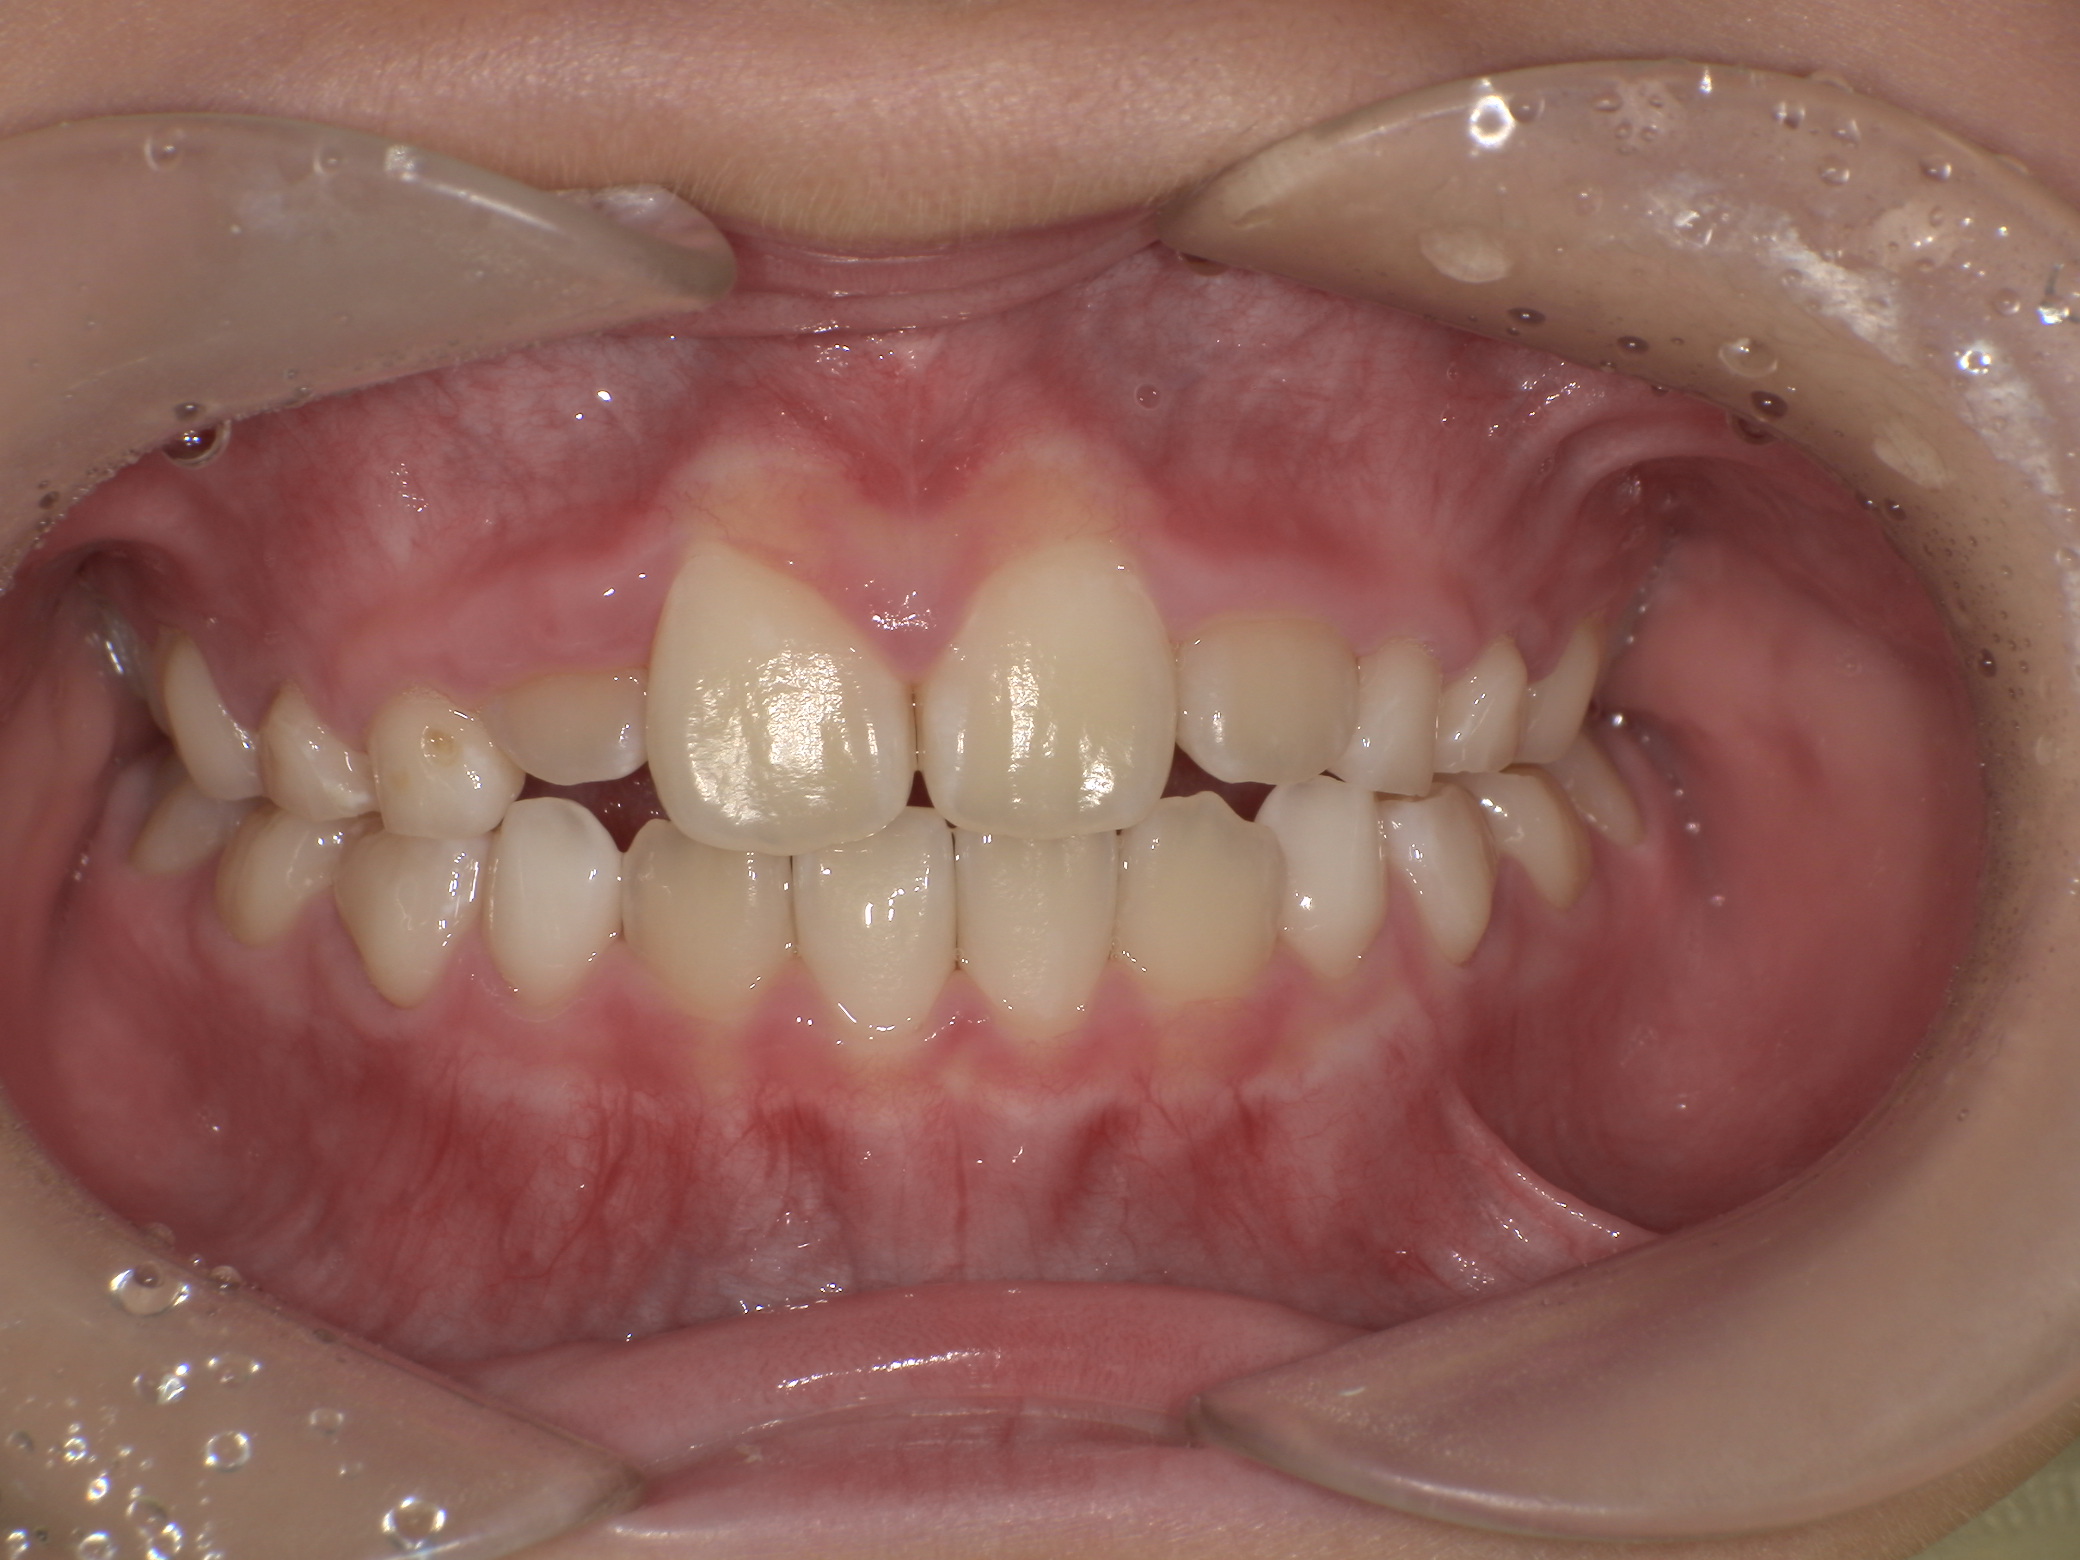

下写真:治療途中(7歳1か月)。反対咬合改善、上顎前歯交換後。

前歯がハの字に広がっている。プレオルソをタイプ1に変更